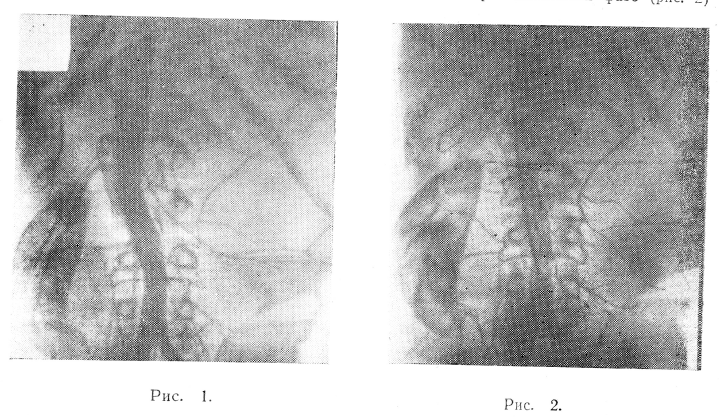

5/II 1969 г. больному произведена общая ангиография почек (рис. 1).

Правую почку снабжают кровью 3 сосуда, отходящие от аорты: два на уровне тела LI и третий на уровне Lui. Левую патологически измененную половину почки питают 4 артерии, из них 2 верхние—почечные на уровне L и 2 нижние — поясничные. Брюшная аорта смещена вправо на протяжении от Dxi до Liv на 3—4 см. Тень левой половины почки не дифференцируется, она занята опухолью больших размеров. Сосуды ее вытянуты и оголены на большом протяжении, в периферических отделах опухоли в области нижнего полюса заканчиваются деформированными мелкими сосудами. Основная масса опухоли имеет низкий уровень васкуляризации, несколько лучше снабжаются кровью поверхностные слои новообразования. Артериальный рисунок правой половины почки без особенностей. В паренхиматозной фазе (рис. 2)

она равномерно и интенсивно пропитывается контрастным веществом, слева же отмечается еле заметное контрастирование опухоли. По наружно-нижнему контуру опухоли сохранившаяся нормальная ткань почки становится заметной, проецируясь на крыло левой подвздошной кости. В области тела Lv она соединяется с нижним контуром правой почки, образуя здесь перешеек подковообразной почки. Верхний край опухоли расплывчатый, теряется в области левого подреберья.